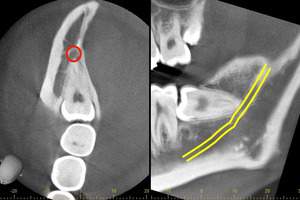

CTの画像です。下歯槽神経と親知らずはほんの少し接触していることがわかります。そのため、この親知らずは2回に分けて抜いていくことにしました。1回目は歯の頭の部分だけを切るだけになります。2回目は1−3ヶ月経ってから行います。

1回目で頭の部分を取ったスペースに歯が伸びてきますので、下歯槽神経と離れたかどうかを再びCTで確認して、残りの根の部分を抜いていく方法になります。

麻布十番歯科でのCT画像。親知らずの生え方を確認し2回に分けて抜歯を行う方法を選択